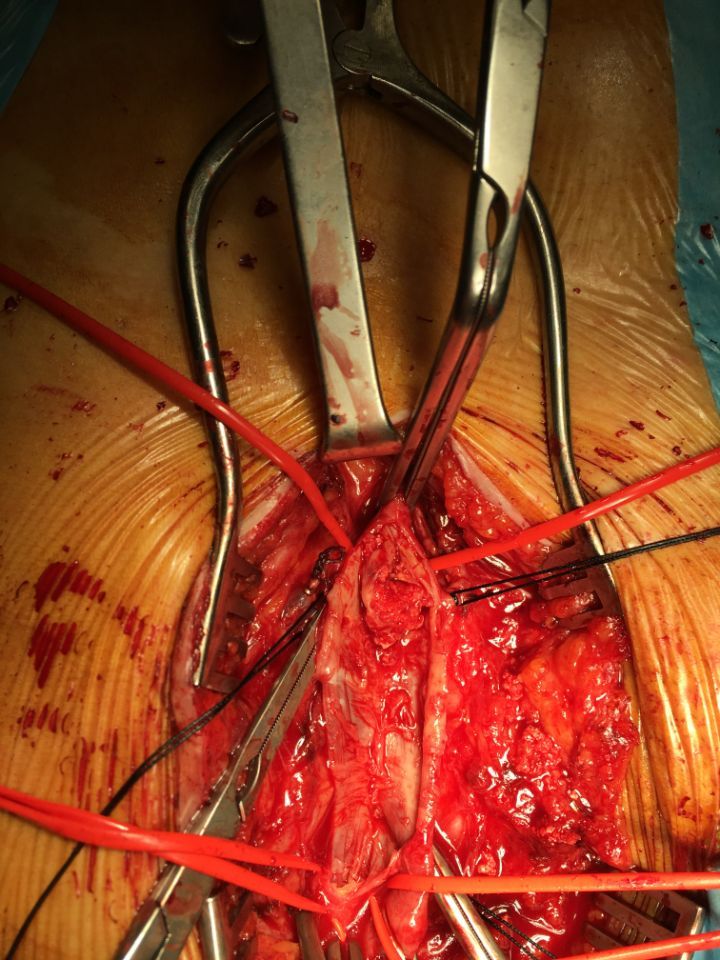

Ecco alcune immagini degli interventi eseguiti dal Dottor Viglione presso il suo studio a Cuneo.